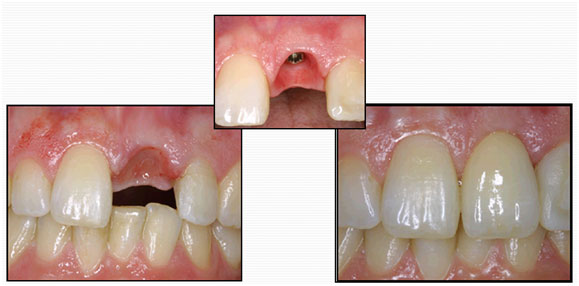

Dental Implants in Karachi: What You Actually Need to Know

Losing a tooth changes more than you expect. It's not just about the gap in your smile, though that's uncomfortable enough on its own. It affects how you chew, how you speak, how confident you feel in a conversation, and over time, it can affect the health of the surrounding teeth and jawbone in ways [...]

Dental Implants at Altamash Dental Clinic: Smiles Re-made, Confidence Restored

We’ll all sooner or later, at one time or another, lose a few teeth here and there, to decay, to an accident, or just to wear and tear

Smile Strong: Why Dental Implants Are the Gold Standard in Tooth Replacement

Missing teeth not only affect your appearance—they also impact your speech, eating, and confidence. At Altamash Dental Clinic, we believe everyone deserves a full, confident smile. Dental implants offer a natural-looking, permanent solution that feels just like real teeth. In this article, we will discuss what implants are, the benefits they offer, and why Altamash [...]

Why Dental Implants by Altamash Dental Clinic are the Best Option for Your Smile

Lost teeth can ruin your smile, besides ruining your self-confidence, oral well-being, and quality of life. Dental implants offer a permanent way to revive your smile and function. Altamash Dental Clinic employs experts to provide high-quality implants tailored to your specific requirements. Whether you are missing a single tooth or many, our trained staff aims [...]

Say Goodbye to Gaps: Transform Your Smile with Dental Implants at Altamash Dental Clinic

With dental implants, a missing tooth in the oral cavity can now be restored using some of the most advanced prosthetic solutions.